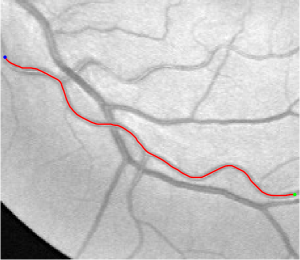

In this paper, we propose a coherence-penalized minimal path model, where the associated minimal paths favour to pass by a vessel that is located in the flatten region of an external feature map. We observe that along a piece of retinal vessel, the values of gray levels vary slowly. More specifically, retinal arteries have lower contrast of gray levels than veins due to the blood materials and imaging modality. In other words, in some extent the arteries and veins are distinguishable in terms of vesselness values. Such an observation can be used to solve the short branches problem that the minimal paths associated to a metric may pass through segments belonging to different vessels as shown in Figs. 1b and 1c. Fig. 1d shows the result from the proposed method, which can avoid such problem. Fig. 1a gives the artery-vein (AV) groundtruth. In this paper, we denote by blue and green dots the source and end points respectively.

Validation. We validate our minimal path model on respective 54 and 30 patches obtained from the DRIVE [14, 15] and the IOSTAR [16] datasets with AV groundtruth. Each artery involved in these parches locates near a vein or crossing it at least once. Our goal is to extract the artery between two given points. In order to get the quantitative evaluation, we first convert each continuous spatial path to an 4-connected digital path which is considered as a pixel collection. We denote by the collection of digital path pixels inside the artery groundtruth map . Thus, a measure can be simply defined as , where and mean the respective number of elements involved in and . We compare our model to four existing minimal path models: the isotropic Riemannian (IR) model [1], the anisotropic radius-lifted Riemannian (ArR) model [4], the isotropic orientation-lifted Riemannian (IoR) model [5] and the curvature-penalized (CuP) model [7]. The construction of these metrics are based on the OOF outputs [12]. Note that a centerline-based potential is chosen so that we remove the radius dimension of [5] to reduce computation complexity. The results in terms of the score are presented in Table 1, including the average (Avg.), maximum (Max.), minimum (Min.) and standard deviation (Std.) values. In both DRIVE and IOSTAR datasets, our method can achieve the best performances thanks to the coherence penalization. Note that in Table 1, we evaluate our method by using the refined paths instead of using the original coherence-penalized minimal paths. For comparisons in visualization, we show the minimal paths from the ArR metric , the CuP metric and the proposed coherence-penalized metric on three retinal patches as shown in Fig. 3. The targeted artery vessels which cross veins at least once are labeled by red color in column 1. The paths shown in column 4 from the proposed metric are results after refinement. One can claim that our method indeed can catch expected arteries while other metrics fall into the traps of short branches combination.